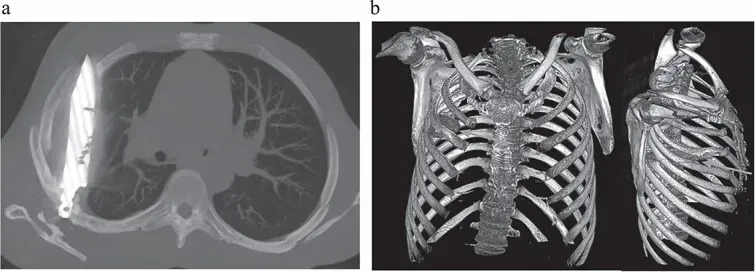

刀片从患者背侧的第五和第六根肋骨之间滑入,随后卡在了那里,刀尖则位于胸腔前侧的第三和第四根肋骨之间。CT扫描显示,其肩胛骨及多根肋骨存在已愈合的骨折。刀片周围被层层脓液及坏死或濒死组织所包裹。

这张 CT扫描图(左)显示了男子胸腔内遗留的刀片,而三维重建的胸部 CT图像(右)则同时展示了这把刀及其引发的相关骨骼损伤图片来源:Kivuyo et al. J Surg Case Rep.2025 May31;2025(6):rjaf325; CC BY4.0